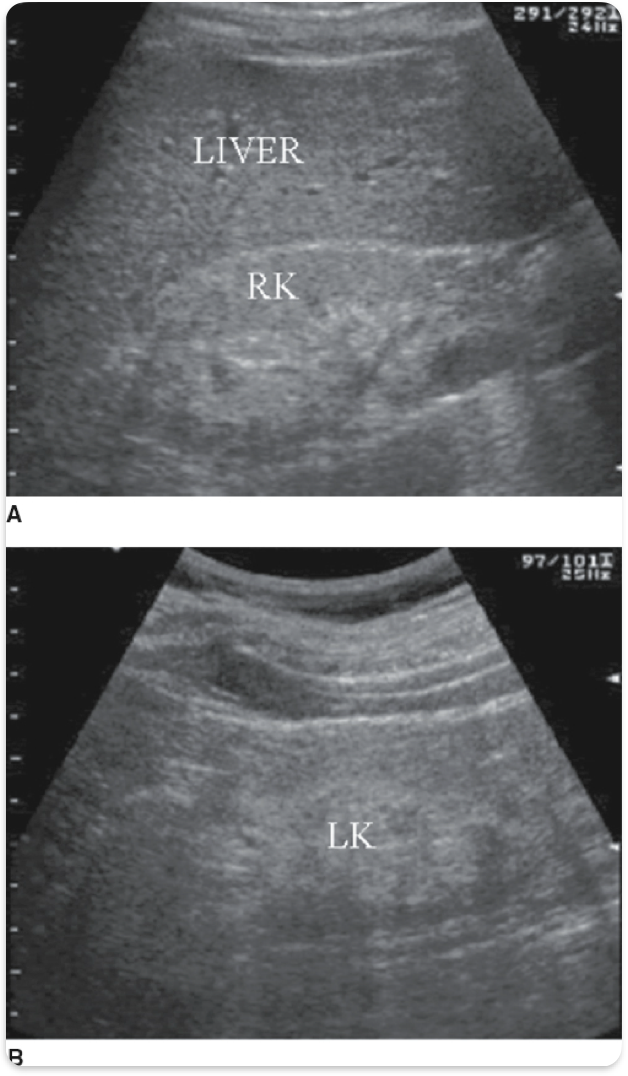

Chronic kidney failure. Small, echogenic. Cortical thinning. Loss of Cortico- medullary differentiation. Renal cysts